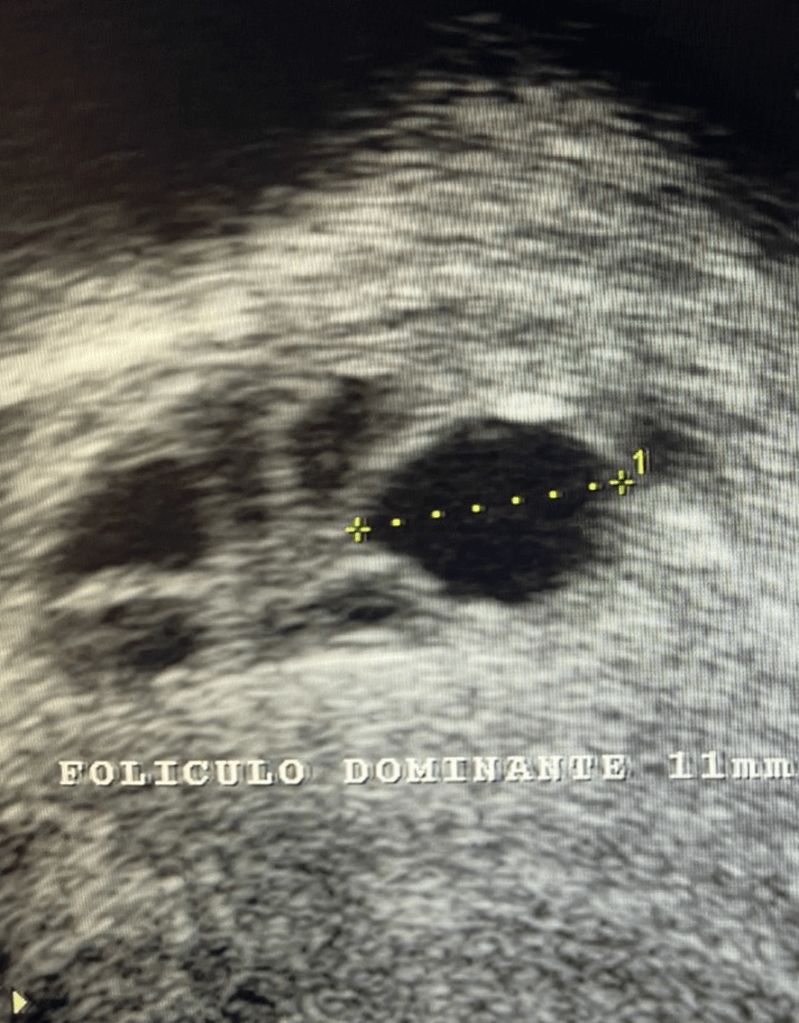

La primera imagen ecográfica de un embarazo la podemos obtener a las 4 semanas de gestación, cuando la embarazada solo lleva 2-3 días de atraso menstrual. Corresponde a una pequeña burbuja negra rodeada de un fino anillo blanco que se encuentra en la cavidad uterina. Suele medir unos 3 mm. Se le llama saco ovular.

Clínica ginecológica Dr. Francisco Valdivieso.